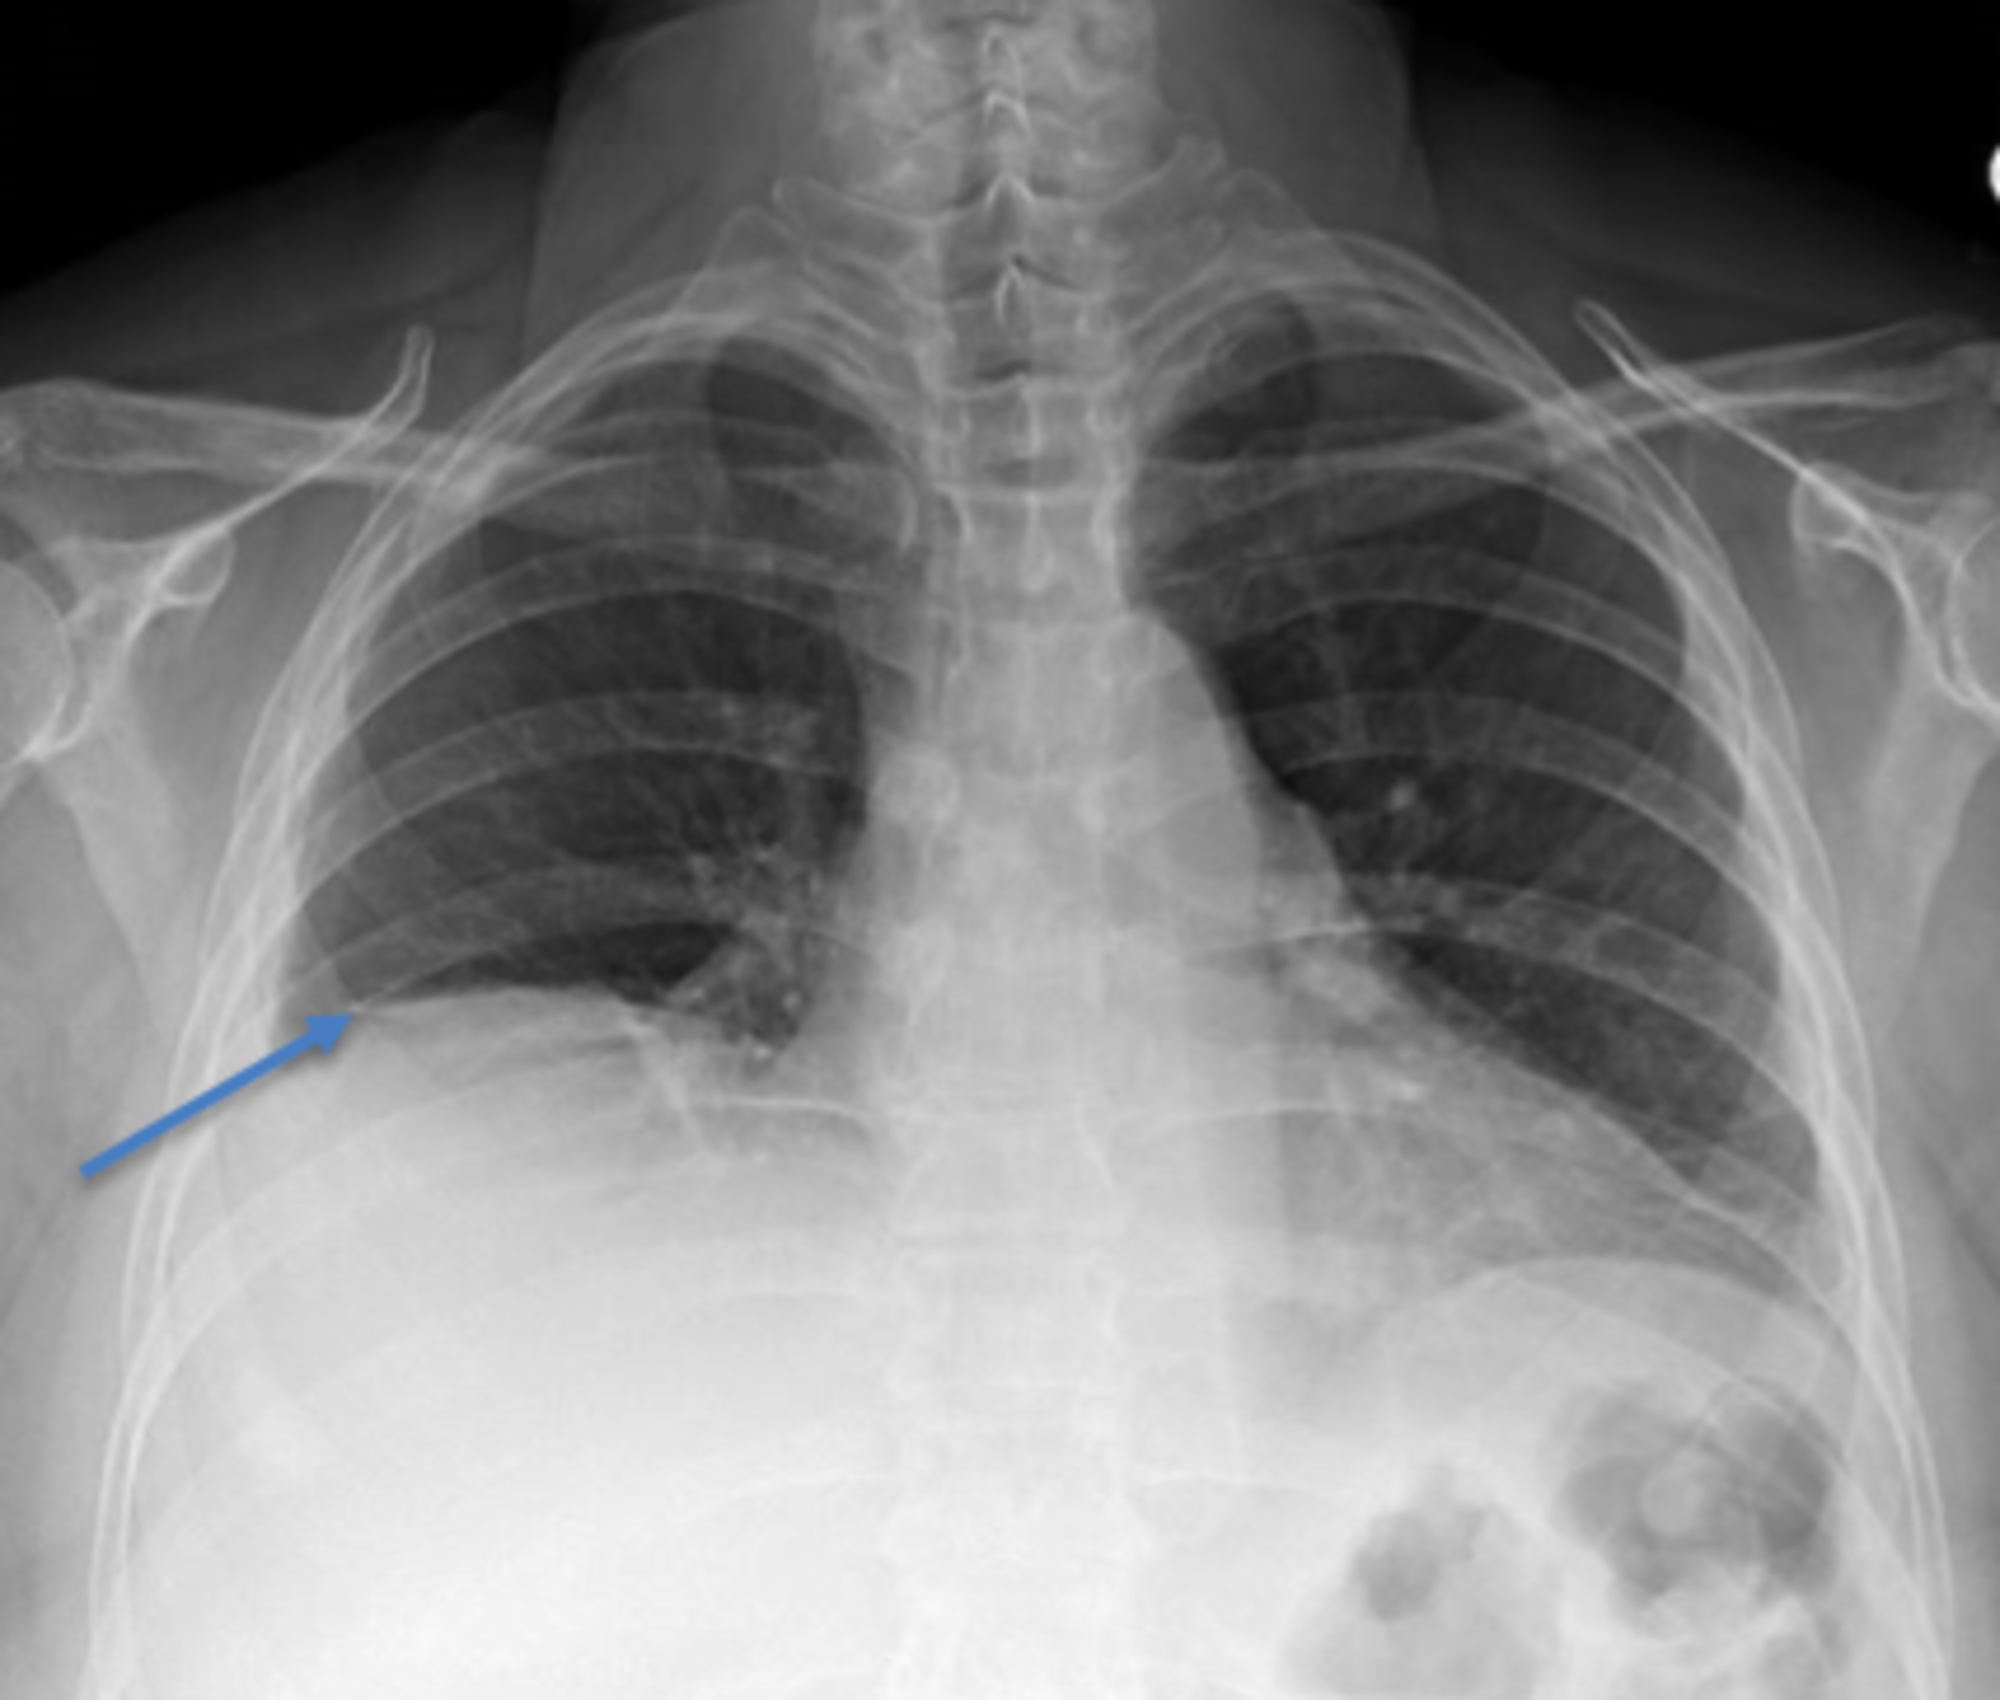

Pneumoperitoneum and subphrenic abscess are two important differential diagnosis of this radiographic sign which can be excluded out when normal plicae circulares or haustral markings of the colon is seen under the right diaphragm. If youre experiencing mild discomfort in your diaphragm take a few minutes to concentrate on deep breathing. Treatment depends on the type of hiatal hernia you have and on your symptoms.

Place one hand on your abdomen and breathe deeply. Reduced number of alveoli air sacs required for normal breathing. In severe cases when there is no simple treatment that can relieve dyspnea your doctor may prescribe morphine. Congenital diaphragmatic hernia CDH. There is usually a long history of heavy smoking. Shortness of breath may be accompanied by wheezing. Diaphragmatic dysfunction caused by transverse myelitis or leukemic infiltration of the cervical spinal cord in a patient with leukemia and shortness of breath. To treat phrenic nerve irritation This condition can be managed with a breathing pacemaker which takes over the responsibility of sending messages to the diaphragm. The cause for shortness of breath was thought primarily due to stable angina on tread mill test positive finding but Chilaiditis syndrome should also be considered as a cause for the shortness of breath.

The rise in intraabdominal pressure further increases intrathoracic and lung volume by pushing the lower rib cage outward. In severe cases when there is no simple treatment that can relieve dyspnea your doctor may prescribe morphine. Diaphragmatic dysfunction caused by transverse myelitis or leukemic infiltration of the cervical spinal cord in a patient with leukemia and shortness of breath. Diaphragmatic plication a surgical procedure that pulls the diaphragm down by introducing a repeated series of continuous sutures across the diaphragm and pulling the muscle taut. A bedside fan or open window with a breeze are also simple but very effective treatments to lessen dyspnea. Depending on the severity of injury to the diaphragm some doctors recommend non-surgical options to treat the breathing issues associated with diaphragm weakness and paralysis. P E Pulmonary embolism.